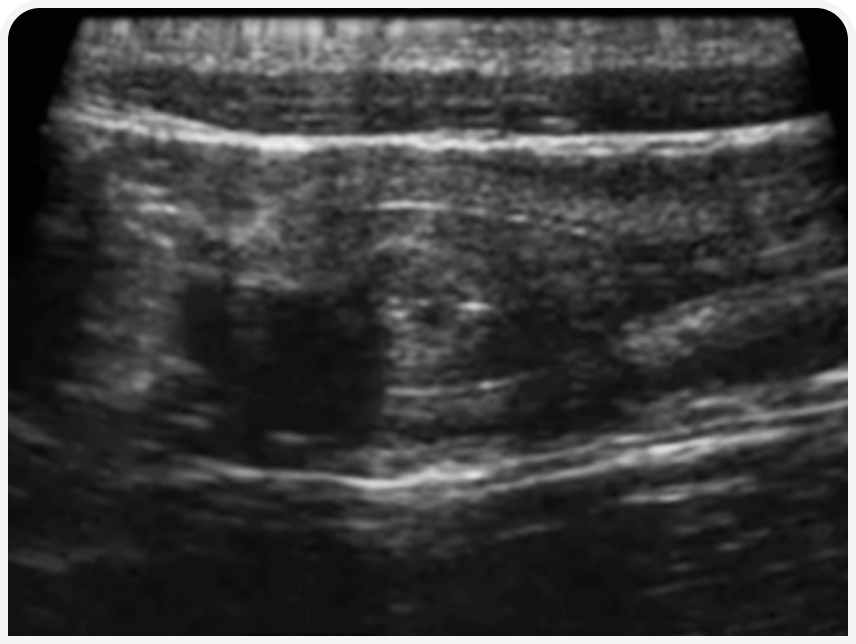

УЗИ в течку будет максимально информативно для определения ОРС. В этот период в корковом слое яичников начинается рост фолликулов, которые у собак около периода овуляции могут достигать размера 1-1,2 см.

При наличии фолликулогенеза яичник приобретает характерную «уникальную» УЗ-картину, что наряду с признаками течки и картиной вагинальной цитологии позволяет подтвердить диагноз ОРС с максимальной достоверностью.

У некоторых животных в реминантном яичнике могут формироваться кисты, вызывающие персистентную течку. Тогда на УЗИ будут обнаружены единичная/множественные кистозные структуры, поликистоз или киста на фоне роста более мелких фолликулов.

У некоторых животных в реминантном яичнике могут формироваться кисты, вызывающие персистентную течку. Тогда на УЗИ будут обнаружены единичная/множественные кистозные структуры, поликистоз или киста на фоне роста более мелких фолликулов. В начале течки яичники могут не иметь хорошо различимых фолликулов. В таком случае стоит повторить исследование через неделю.